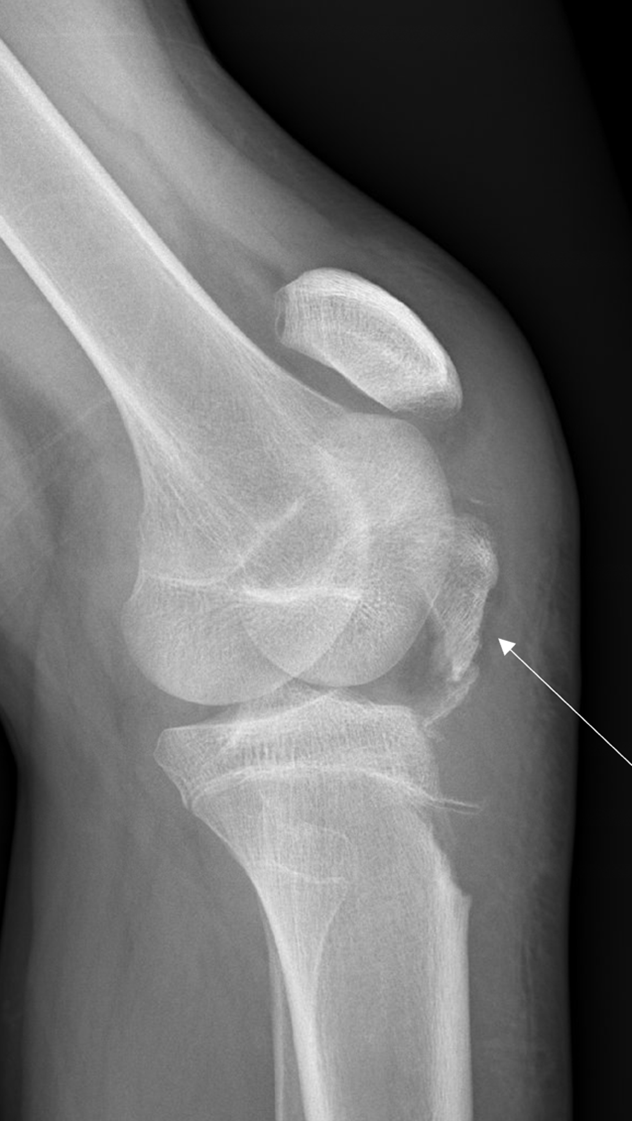

POCUS of the left knee was performed, which was concerning for a patellar tendon rupture and a joint effusion. (Figure 1 and Video 1) In addition, there was posterior acoustic shadowing obscuring part of the patellar tendon concerning for an avulsed bony fragment. (Figure 2) X-rays were performed, which confirmed the suspected diagnosis of a left tibial tubercle avulsion. (Figure 3) The patient was ultimately taken to the operating room for an Open Reduction and Internal Fixation (ORIF) by Orthopedic Surgery and discharged home the following day in a knee brace.

Figure 3. Lateral knee x-ray showing tibial tubercle avulsion (arrow)

Tibial tubercle fractures typically occur in adolescent males after jumping or sprinting. This pathology thought to be due to relative skeletal immaturity relative to anterior cruciate ligament (ACL) strength during strenuous activity.5,6 Proper diagnosis of the fracture is crucial in avoiding complications such as compartment syndrome, atrophy of the quadriceps, or loss of knee flexion due to associated ligament injury.6 These fractures are typically diagnosed on X-ray, but can be missed in skeletally immature adolescents or if the avulsed fragment is small.3,4 Second-line imaging such as computed tomography (CT) or magnetic resonance imaging (MRI) may be needed to confirm the suspected diagnosis. However, MRIs may be very difficult to obtain emergently (or at all) in the ED, and CTs expose the patients to ionization radiation. We propose that POCYS should be considered to expedite detection of these fractures when evaluating patients with acute knee injuries.